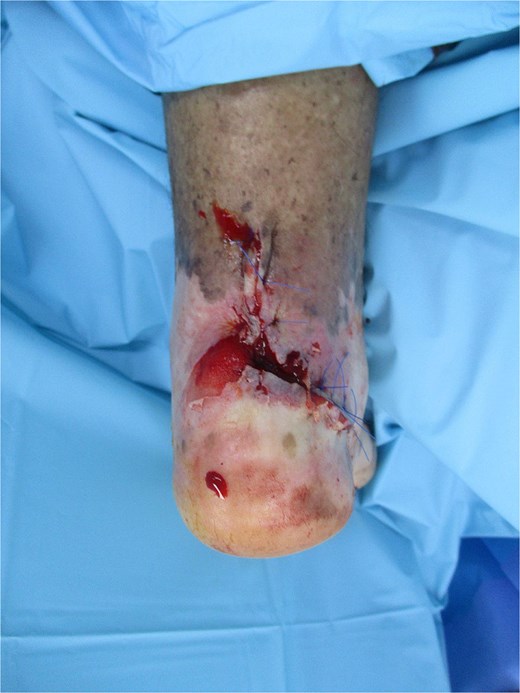

Vascular imaging showed atherosclerosis with femoral stenoses and posterior tibial artery occlusion; biopsy confirmed invasive cSCC (Fig. 2). An excisional biopsy during debridement of the ulcer edge was performed after vascular imaging and prior to definitive surgery, which confirmed invasive cutaneous SCC. Histopathology revealed a well-differentiated squamous cell carcinoma, pathological stage pT2Nx, and measuring 2.1 × 1.5 cm with a depth of invasion of 8 mm. The tumor reached anatomic level IV, invading the reticular dermis. No lymphovascular or perineural invasion was identified. The carcinoma was focally present at the lateral margin and 1 mm from the deep margin. Whole-body positron emission tomography/computed tomography and magnetic resonance imaging of the left foot showed only local inflammatory changes without evidence of regional or distant metastasis. Following multidisciplinary tumor board discussion, the patient underwent re-excision to achieve clear margins, which confirmed absence of residual carcinoma. Given the focally positive margin in the initial specimen, adjuvant radiotherapy was delivered post-operatively. Routine laboratory and radiographic investigations were unremarkable. At 4 months post-surgery and adjuvant radiotherapy, the patient remained disease-free.

Intraoperative view showing wide local excision of the retrocalcaneal ulcer; histology confirmed well-differentiated SCC (pT2Nx) with 8 mm invasion depth; defect prepared for regional advancement flap coverage.